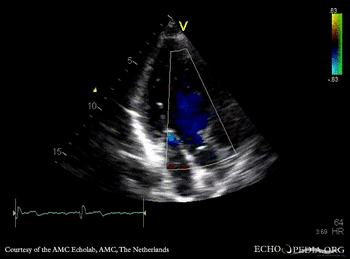

A3CH: subvalvular membrane A3CH with Color Doppler: high velocity flow in LVOT